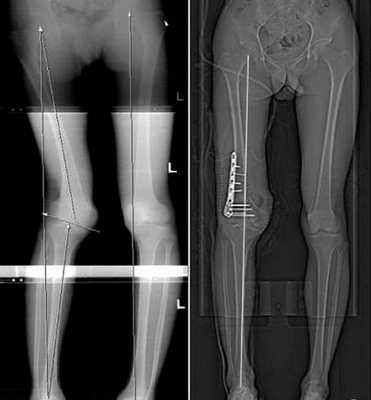

При переломах необходима тщательная репозиция костных отломков и гипсовая иммобилизация. При выраженных деформациях костей показано проведение хирургического лечения - корригирующей остеотомии с интрамедуллярным или накостным остеосинтезом.

При выраженной деформации костей проводят корригирующую остеотомию, которая помогает исправлять форму, размер конечностей. Во время хирургического лечения пораженная кость рассекается, исправляется ее форма и далее она фиксируется специальными конструкциями, то есть проводят остеосинтез.

Он бывает двух видов: накостный и интрамедуллярный. В первом случае фиксирующая конструкция находится в теле больного, но снаружи кости. Во втором случае изделие полностью зафиксировано внутри кости.